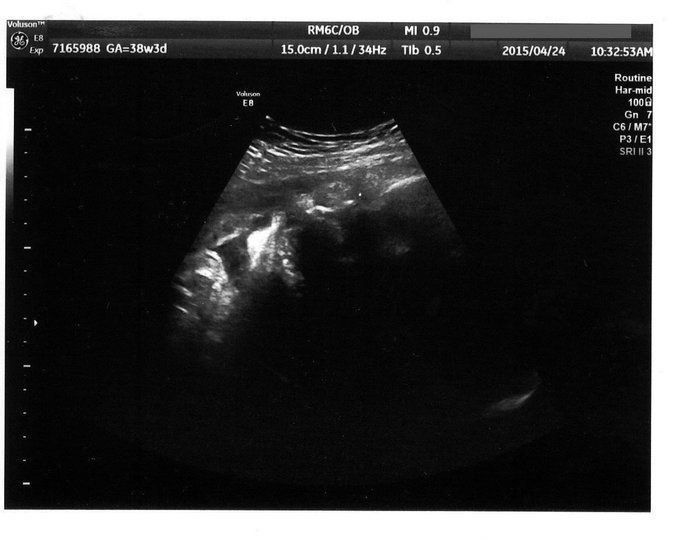

宝物の息子とはおなかのなかで対面してた!エコー写真で出会いからこれまでを振り返る -